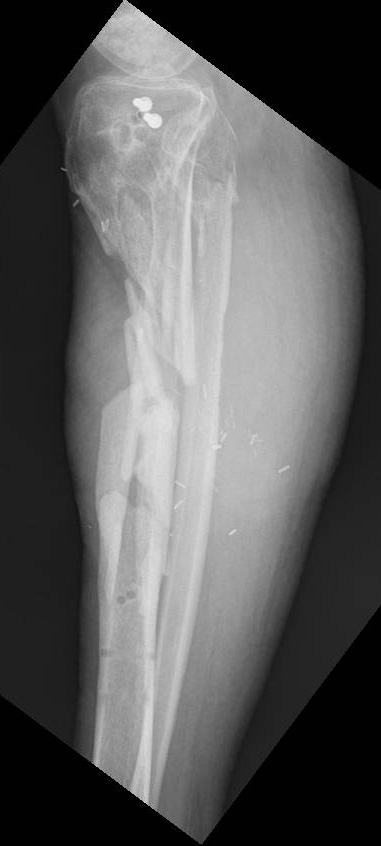

Nonunion: Tibia Case 3

Treatment in ProgressThis series of x-rays shows treatment using Ilizarov bone transport. A large segment of infected bone in the upper tibia had been removed. The lower tibia had been split into two segments, and these segments were slowly moved upward using the llizarov external fixator until the bone was restored.